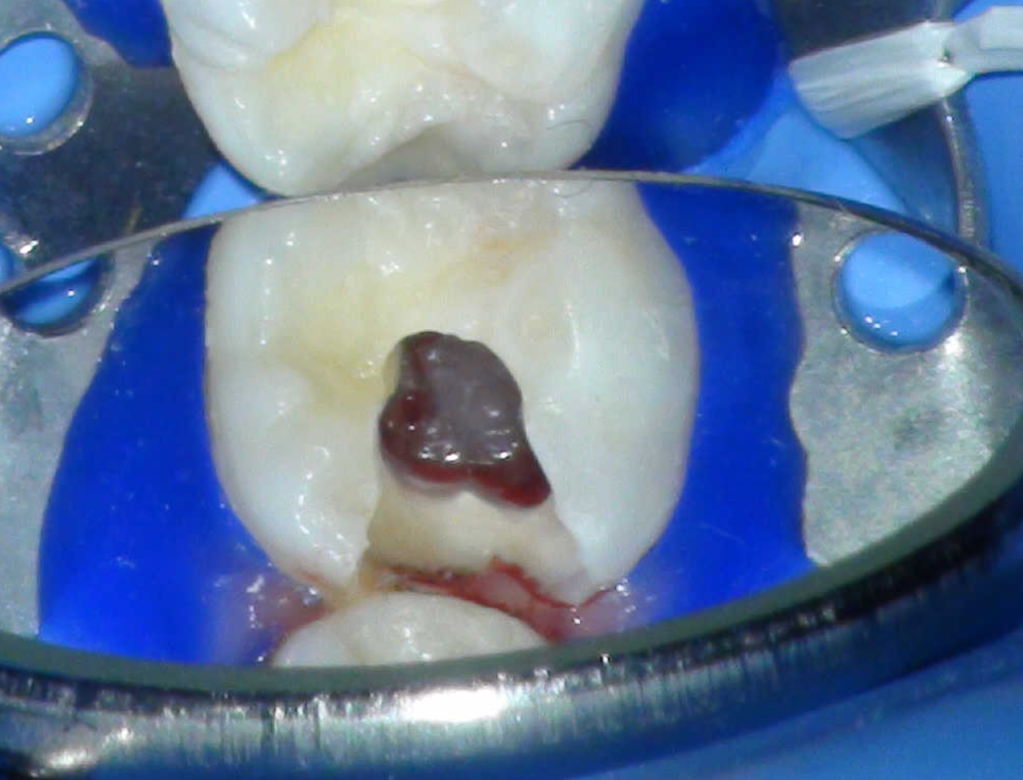

Pulpotomía biodentine + reco preendio

Pulpotomía diente temporal